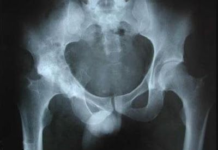

STC (Sinovitis transitoria de la cadera)

Una de las causas mas frecuentes en la cual se manifiesta esta enfermedad es la cojera a causa de dolores en la cadera o...

La enfermedad de Legg -Calve -Perthes

Esta enfermedad es causada por grados diversos de la cabeza femoral y por isquemia, es uno de los trastornos de la cadera autolimitado. La...